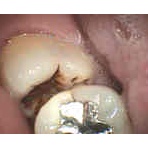

親知らずは抜くべきか?

薄い骨にもインプラント